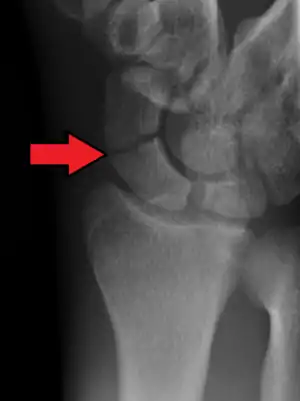

A subtle scaphoid fracture

A more obvious scaphoid fracture on a scaphoid view X ray